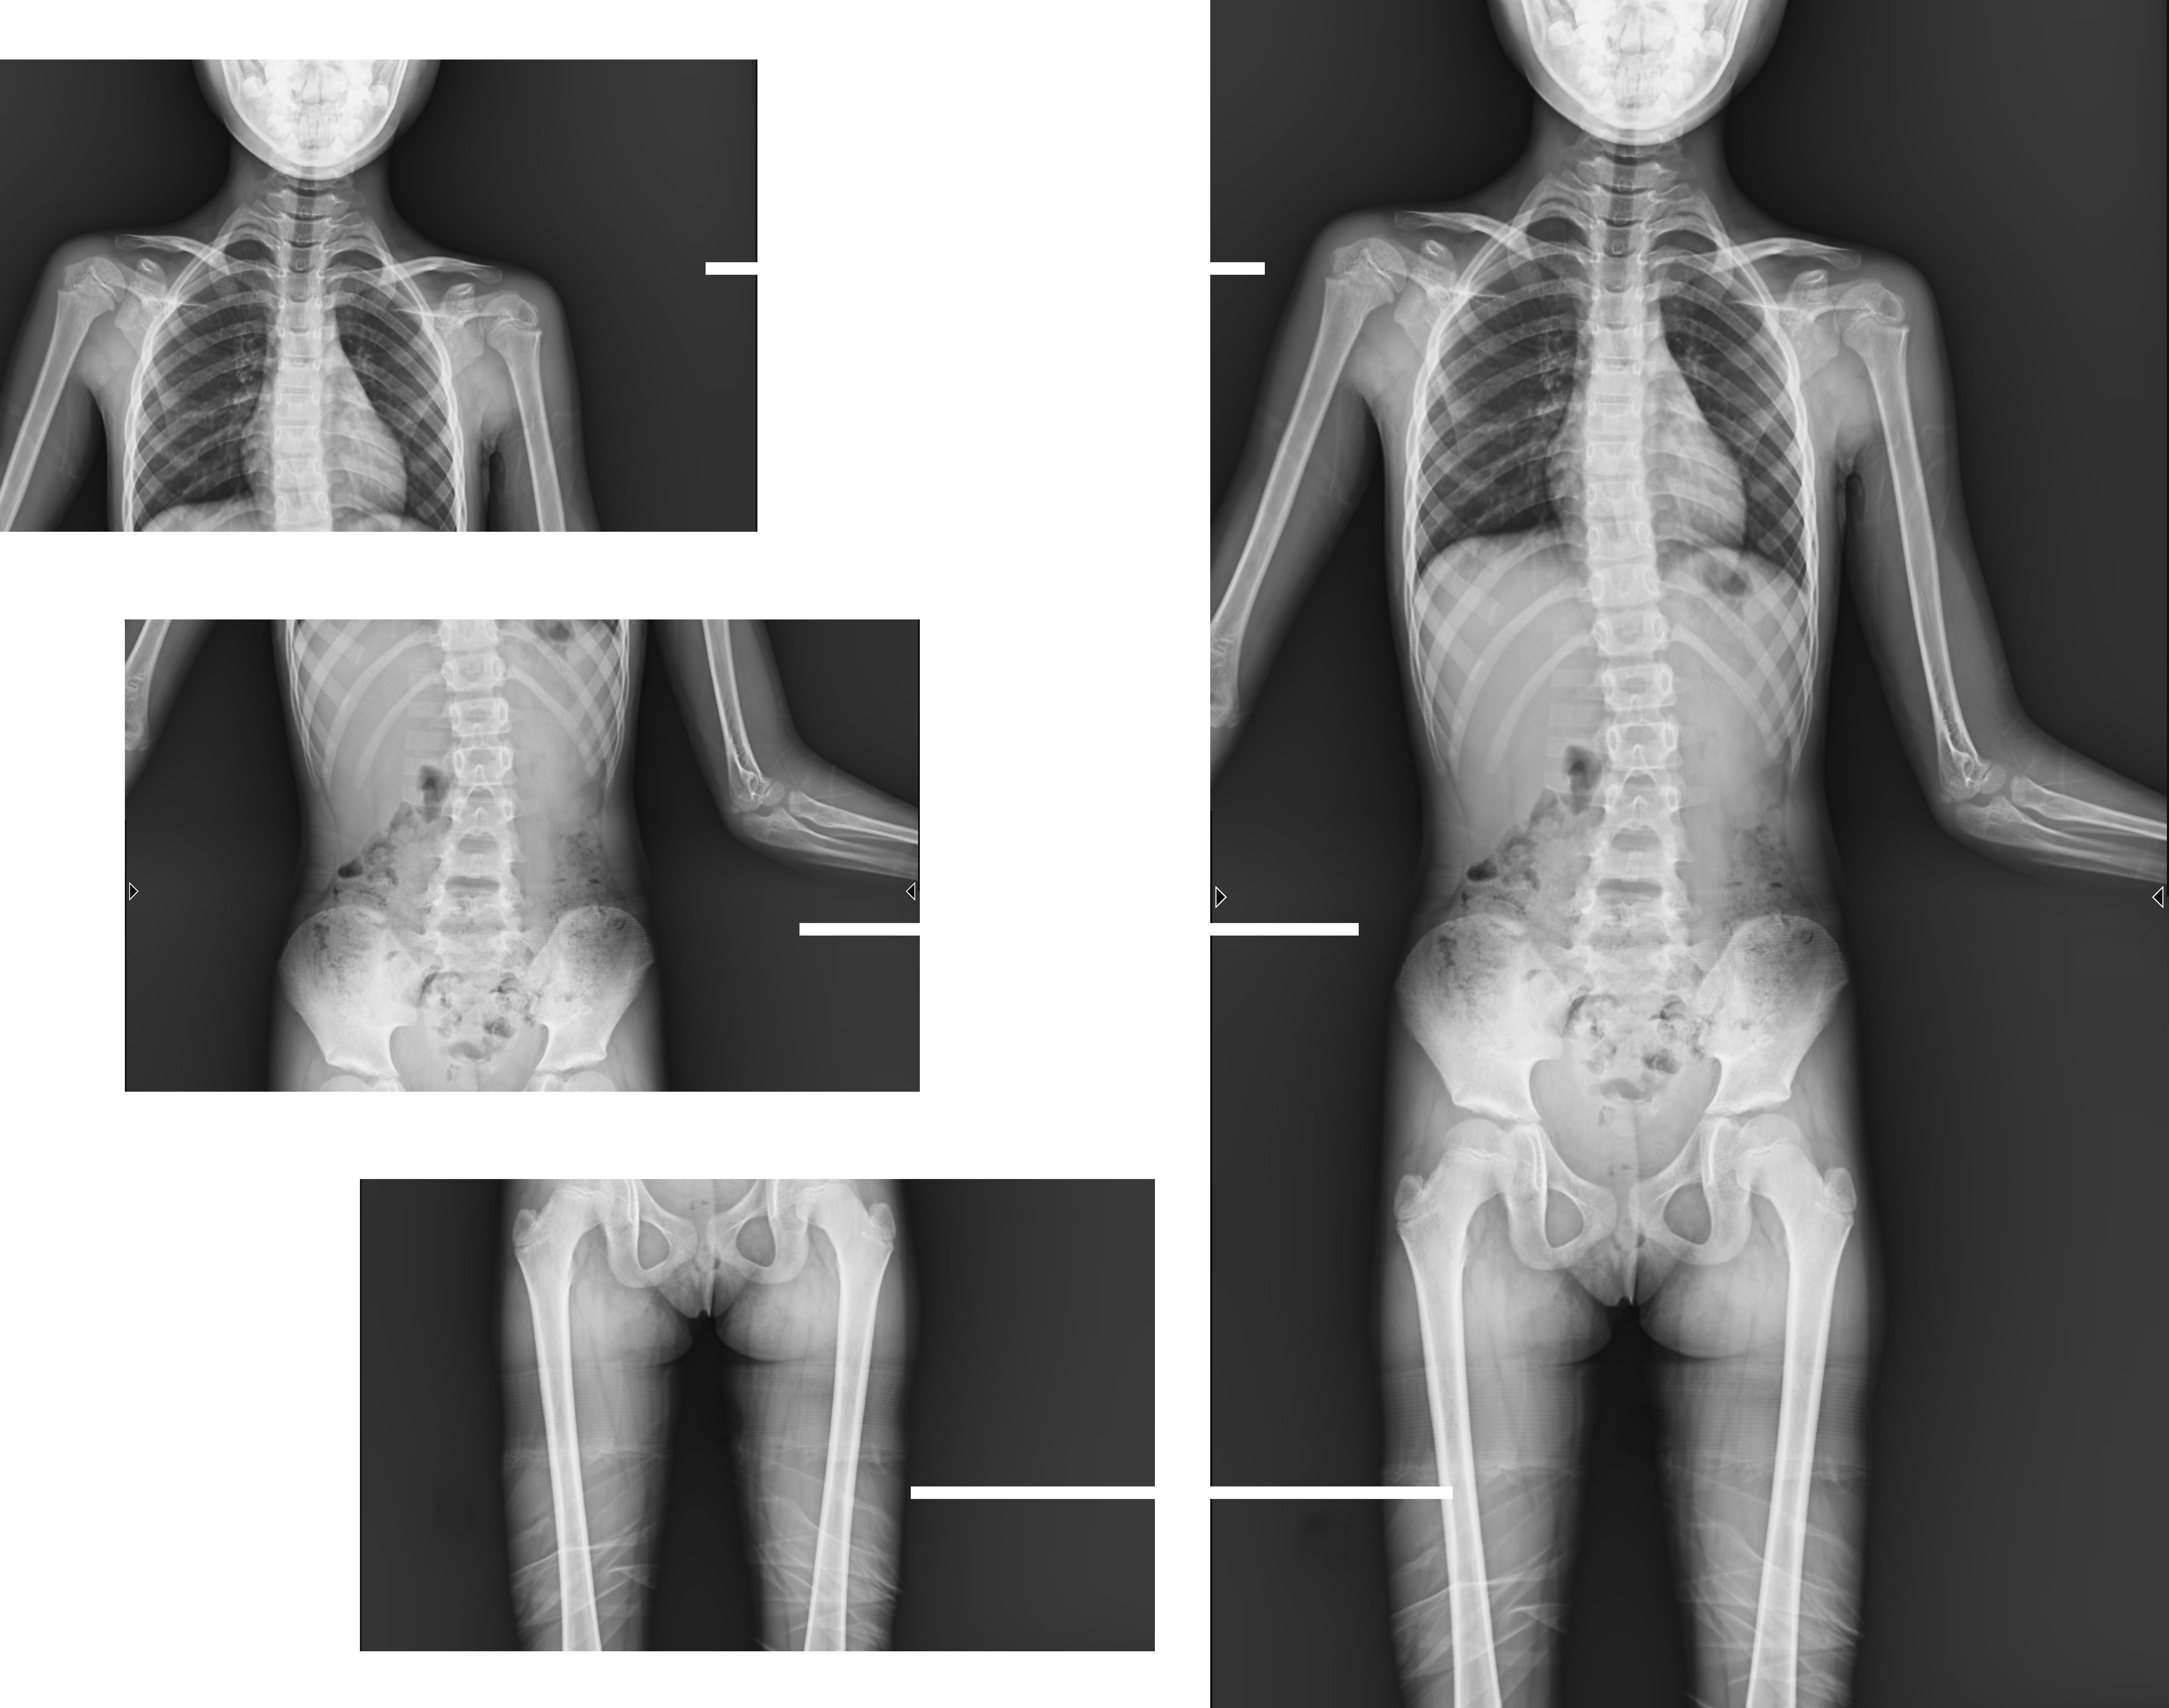

近年來,多發(fā)于青少年的脊柱側彎畸形,及骨性關節(jié)炎、風濕性關節(jié)炎、雙下肢畸形(膝關節(jié)內(nèi)外翻、X型O型腿等)等骨科常見病發(fā)病率逐年增長,病癥常常累及下肢髖關節(jié)、膝關節(jié)、踝關節(jié)三個負重關節(jié),嚴重危害患者健康